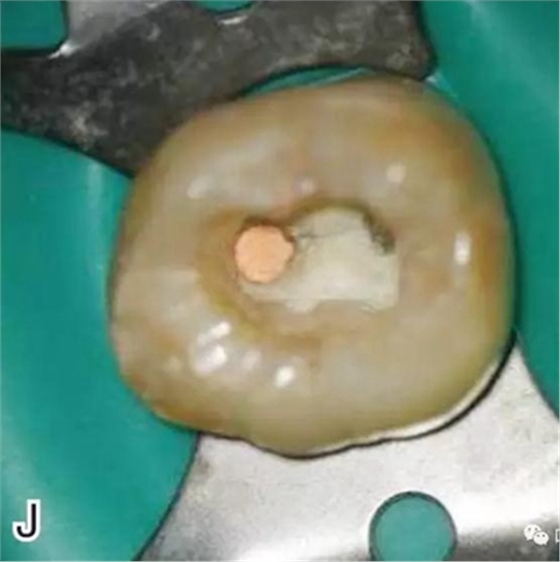

8、熱牙膠根中上段的充填

在完成根尖段的充填后,使用熱塑牙膠注射儀對(duì)根管中上段進(jìn)行分層充填,一般分2~3次完成充填,每次充填均使用相應(yīng)直徑大小的垂直加壓器進(jìn)行加壓。拍片確認(rèn)充填效果(圖8)。

圖8 熱牙膠根中上段的充填,A、B.注射儀注射中段熱牙膠

C、D.垂直加壓器加壓 E、F.注射儀繼續(xù)注射上段熱牙膠

G、H.垂直加壓器加壓 I、J.完成根中上段的充填